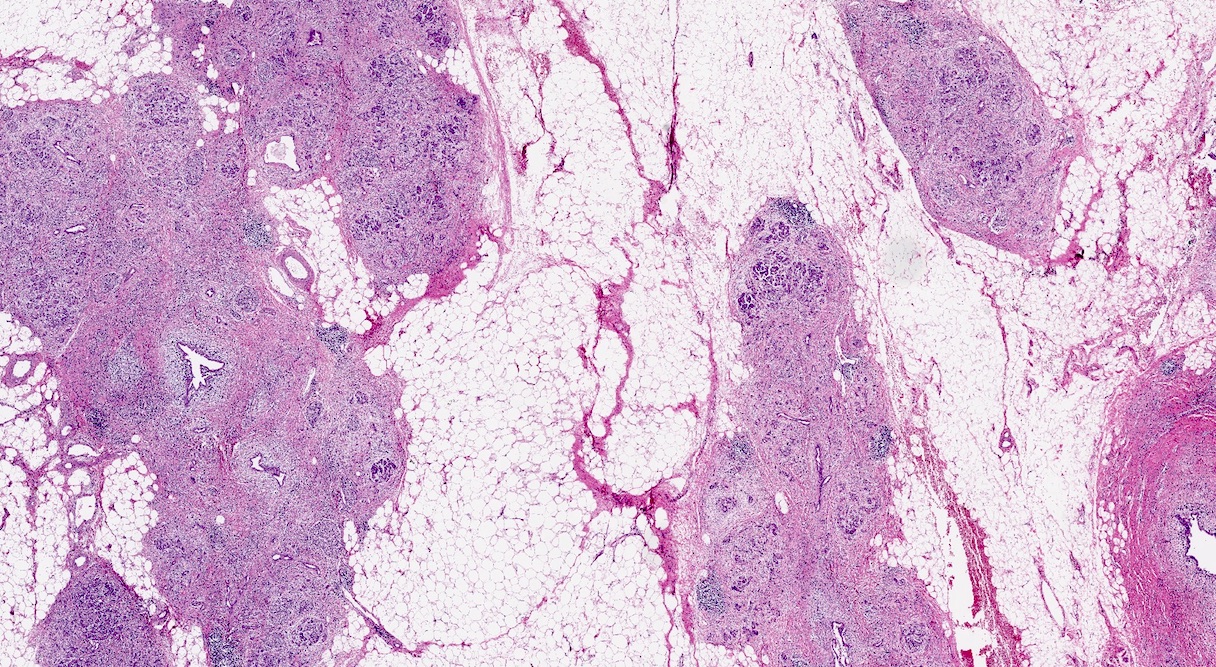

Microscopic (histologic) description

- Triad of cardinal features: fibrosis, loss of acinar tissue, duct changes (Pancreatology 2020;20:586)

- Fibrosis is initially perilobular; during disease progression, it involves the pancreatic lobular units, eventually replacing the acinar parenchyma (so called intralobular fibrosis)

- Acinar tissue may be replaced by fibrosis or fatty tissue; the latter process (lipomatous atrophy) is more frequently seen in hereditary pancreatitis (Pathologica 2020;112:197)

- Loss of acinar tissue predates that of pancreatic islets, which are often seen isolated in fibrosis or fatty tissue in advanced cases

- Ductal changes include distortion of ductal profiles, ectasia, presence of intraluminal concretions of amorphous material (so called protein plugs), squamous metaplasia, intraductal calcification

- Foci of low and high grade pancreatic intraepithelial neoplasia (PanIN) may be encountered

- Foci of periductal chronic inflammation and fat necrosis represent a common finding

- Pseudocysts lined by granulation tissue are common in alcoholic chronic pancreatitis

Microscopic (histologic) images